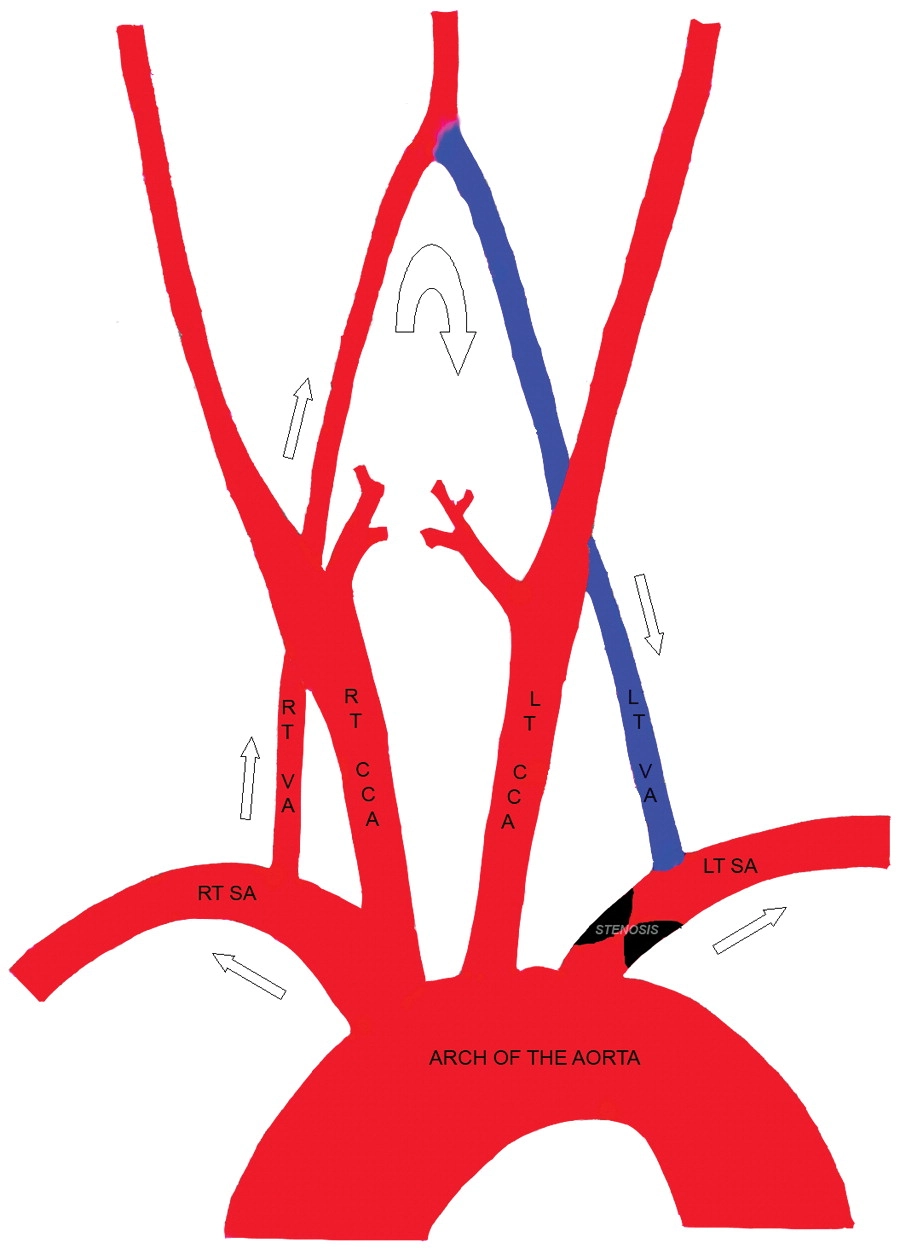

Subclavian Steal Syndrome occurs when blood flow is redirected from the brain to the arm, leading to symptoms like dizziness, weakness, and vision problems.

Images visual examples of subclavian steal syndrome

Visual of subclavian steal syndrome often highlight reduced cerebral blood flow and compensatory circulation changes.